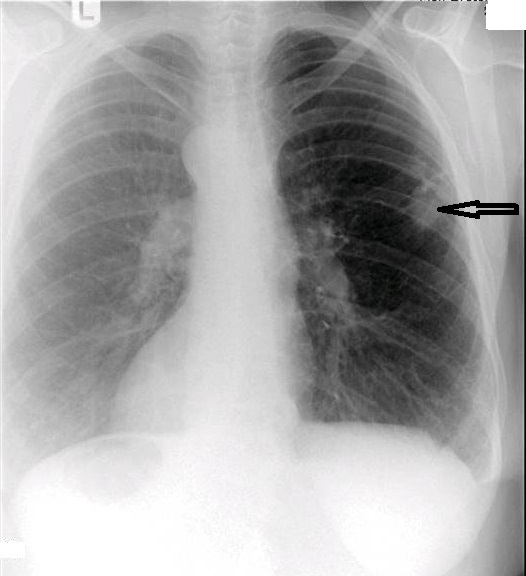

The chest series was obtained and again demonstrated the lesion noted previously on the thoracic spine. The lesion is more clearly seen on figure 3, the PA chest projection. It measured 3.0 cm in the long axis, and the border was not particularly sharp and appeared somewhat spiculated on close inspection (open arrow points to lesion). No calcifications were noted within the lesion. This finding is worrisome, as benign granulomatous lesions, which are often discovered incidentally, frequently manifest some degree of calcification, while more aggressive lesions exhibit calcification less often. Figure 4 again demonstrates the thoracic spine compression fractures.

It was recommended that the patient undergo a chest CT examination in order to more thoroughly investigate the lesion and also be referred to an oncologist or internal medicine physician for follow-up. A chest CT was performed and identified the mass in the right lung. A spiculated border was noted. The lack of any internal calcification within the lesion was confirmed. No definite lymphadenopathy was identified on the CT. The patient was then scheduled for lesion biopsy. The subsequent biopsy revealed that the mass was malignant. This patient is currently awaiting the results of additional testing before treatment options are discussed.